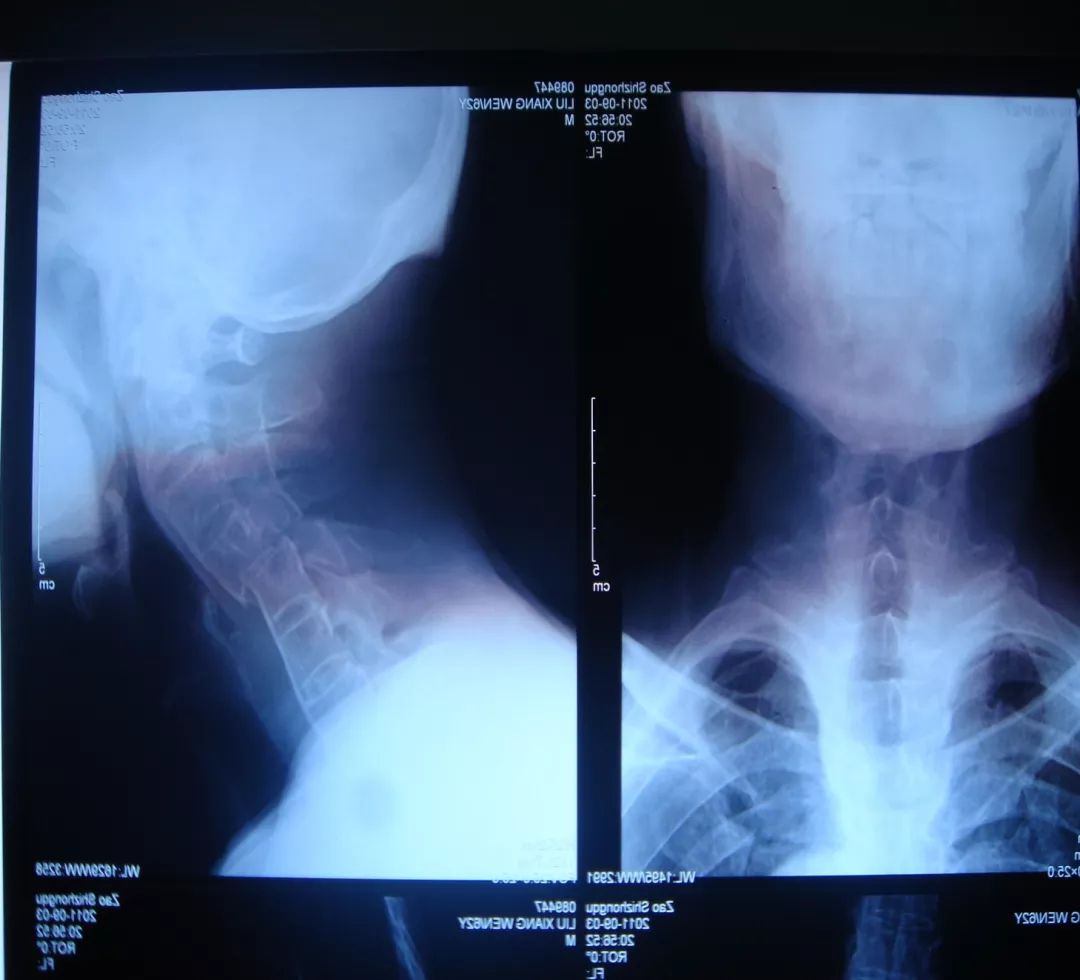

经过全程监护和系统治疗,患者术后恢复良好,骨折解剖复位,复查X线及CT显示固定位置佳,术后3天下地行走,术后4天即出院回家休养。

“宝剑锋从磨砺出,梅花香自苦寒来。”目前,枣庄市立医院脊柱外科在上颈椎损伤治疗方面取得长足发展,对于枢椎齿状突骨折,已能独立开展前路空心螺钉固定、后路Margerl手术、后路椎弓根钉棒固定术,在上颈椎外伤治疗方面处于省内领先。

颈椎骨折脱位前后联合减压固定术